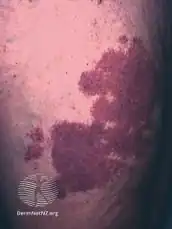

| The back of a hand with prominent port-wine staining | |

| Symptoms | Dark red or purple area of skin with defined borders[1] |

Port-wine stain, also known as nevus flammeus, is a birth mark that presents as a dark red or purple area of skin.[1][3] They occur most often on one side of the face or neck;[1][3] though, any part of the body may be involved.[2] They generally have defined borders and over time may become darker and thicken.[2] Complications may include glaucoma.[2]

They generally presents as a dark red or purple area of skin at birth.[1][3] They occur most often on one side of the face or neck;[1][3] though, any part of the body may be involved.[2] They generally have defined borders and over time may become darker and thicken.[2] Complications may include glaucoma.[2]